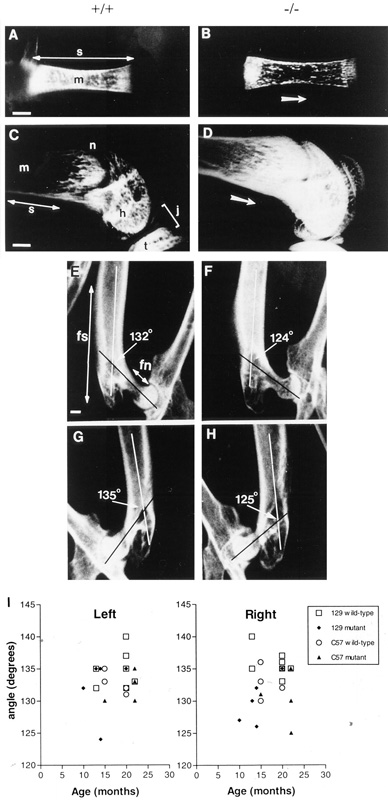

Caption Altered bone content and incidence of coxa vara in Col10a1tm1Ksec/Col10a1tm1Ksec mice. (A-D) Micrographs of the femurs of 2 day (A and B) and 4 week (C and D) wild-type (+/+, A and C) and mutant (-/-, B and D) female mice of 129/Sv background. The opacity of the bony region (white in X-ray image) correlates with the amount of radiographically opaque bone materials. Single-headed arrows in B and D indicate orientation proximal-distal. Abbreviations for bony landmarks: h, distal head (articular condyle); j, knee joint, m, marrow cavity; n, neck; t, tibia; s, shaft, Bar, 0.5 mm. (E-H) Radiographic study of the angle of the femur head of wild-type (+/+, E and G) and mutant (-/-, F and H) mice at 13-14 months (E and F) and 20-22 months (G and H). A decrease in the angle between the neck (fn) and the shaft (fs) of the femur (coxa vara) is observed at both ages. There is always a significant foreshortening of the length of the neck of the femur of the mutant mice shown in F and H. Bar, 1 mm. (I) Measurements of the angle of the head of the the left and right femur of the wild-type and mutant mice at various postnatal ages. Significant unilateral (right) coxa vara, showing varus angulation was found in some mutants.